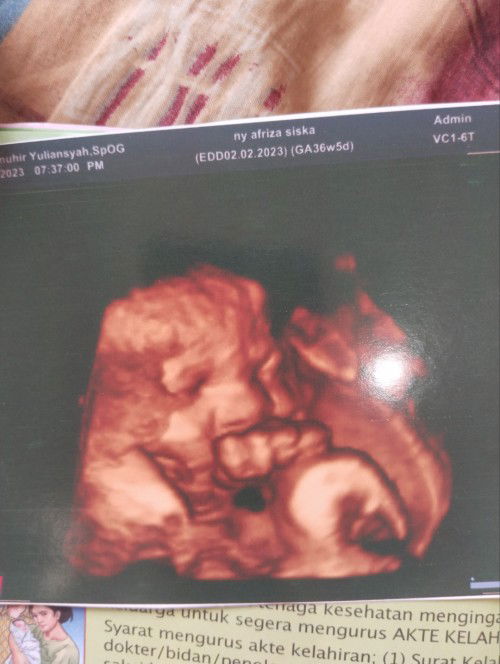

Bun saya hamil 7 bln v tali pusat y melilit 2 d leher. Ada tidak yg tw cara menormalkan tali pusar

Tali pusat kelilit